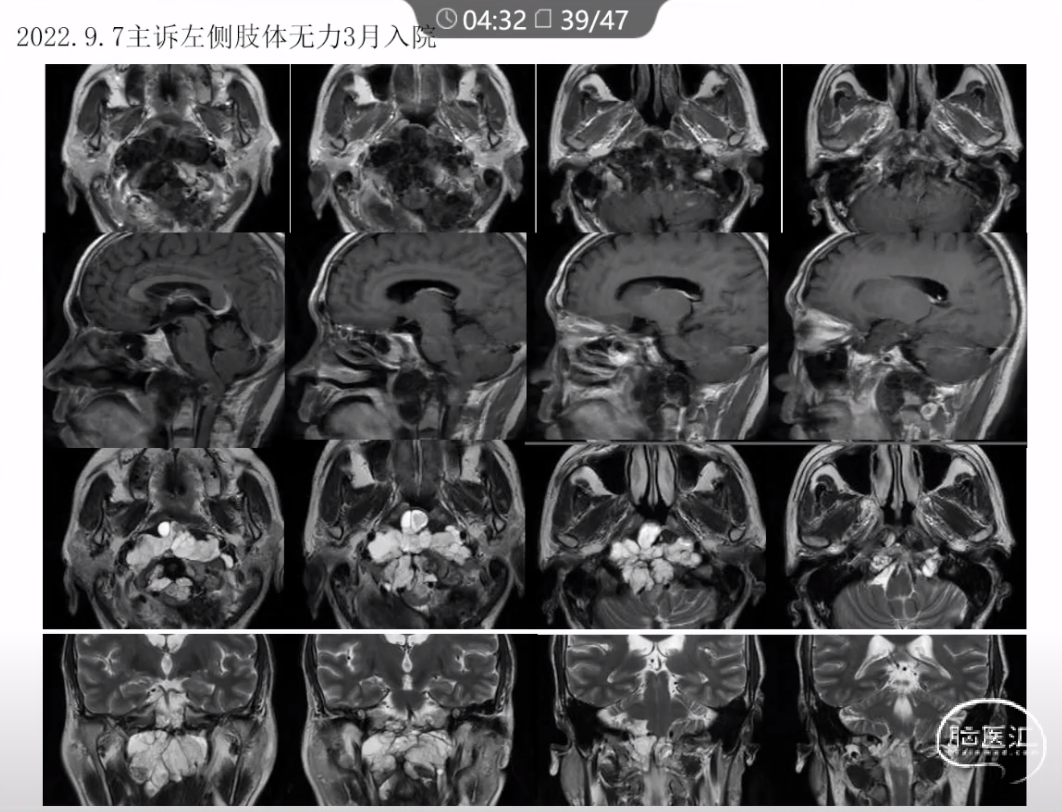

本文主要内容为:脊索瘤临床特点、治疗选择,以及多个手术病例。